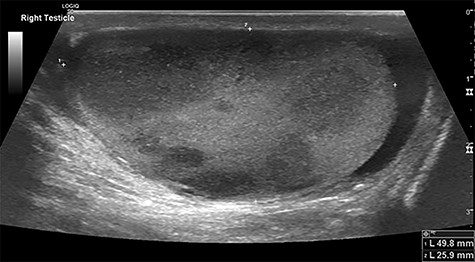

A 71-year-old man presented to the emergency department 3 days after falling from a ladder, having noticed a hard lump on his testicles. His past medical history included: osteoarthritis, hypercholesterolaemia and ‘prediabetes’; he had a family history of ischaemic heart disease. Examination revealed firm non-tender lumps on the right testicle, with no signs of testicular rupture. A subsequent ultrasound scan demonstrated ‘multiple hypoechoic lesions in the right testis (up to 3 cm) suspicious of malignancy’ (Fig. 1). Tumour marker results demonstrated a raised lactate dehydrogenase at 426 but normal beta-human chorionic gonadotrophin and alpha-fetoprotein levels. His liver function tests revealed raised aspartate transaminase (62) and alkaline phosphatase (252) but normal bilirubin levels. The impression was a testicular lymphoma.

Testicular ultrasound of the right testicle demonstrating multiple hypoechoic lesions—the largest measuring 3 cm.